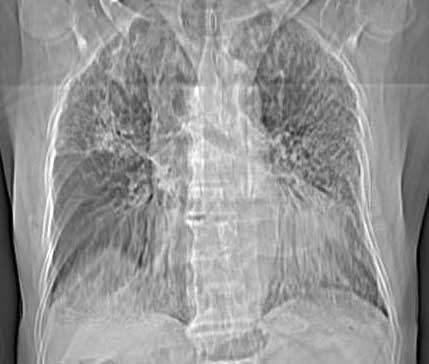

以下是引用同在2006-7-20 21:01:00的发言:[br]间质性肺炎,两肺纤维化,肺气肿。

以下是引用dalianren在2006-7-20 21:23:00的发言:[br]我考虑是肺泡蛋白沉积症:典型表现为两肺内散在片状\"磨玻璃\"样混浊区呈地图样分布.

以下是引用lj0804在2006-7-21 12:57:00的发言:[br]支持[br]我考虑是肺泡蛋白沉积症:典型表现为两肺内散在片状\"磨玻璃\"样混浊去呈地图样分布.